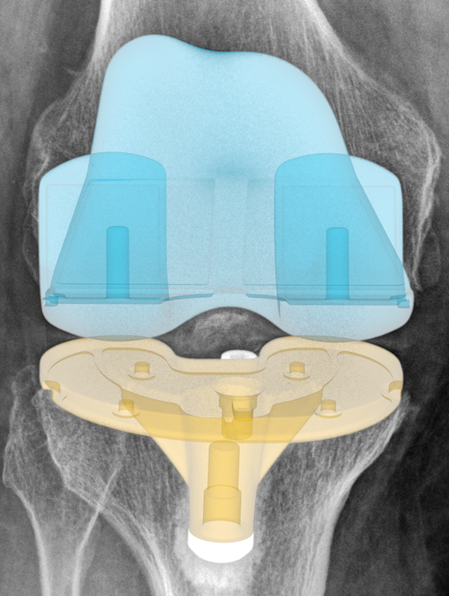

Knee Implant Positioning and Performance Intelligence

RAYLYTIC Image Lab enables high-precision implant positioning and performance such as component alignment, rotation, migration, and wear for faster, more consistent research results.

Knee & leg measurements

- Hip-Knee-Ankle (HKA) alignment angles

- Implant component positioning (6 degrees of freedom)

- Component alignment (coronal & sagittal)

- Leg alignment

- Femoral-Tibia Angle

- Joint line conversion angle

- Distal Tibia Angle

- Proximal femur angle

- Polyethylene wear quantification

- Implant migration/subsidence

Implant Component Positioning Assessment from Standard Radiographs

Precise quantification of femoral component rotation, tibial component rotation, and coronal/sagittal alignment: all derived from routine postoperative AP and lateral X-rays.

Polyethylene (PE) Thickness & Wear Behavior

Tibial component migration

A radiographic measurement that quantifies the displacement of the tibial component relative to the proximal tibia in total knee arthroplasty. Assessed through serial radiographs, migration is measured in both linear (millimeters) and angular (degrees) dimensions across mediolateral (ML) and craniocaudal (CC) axes.